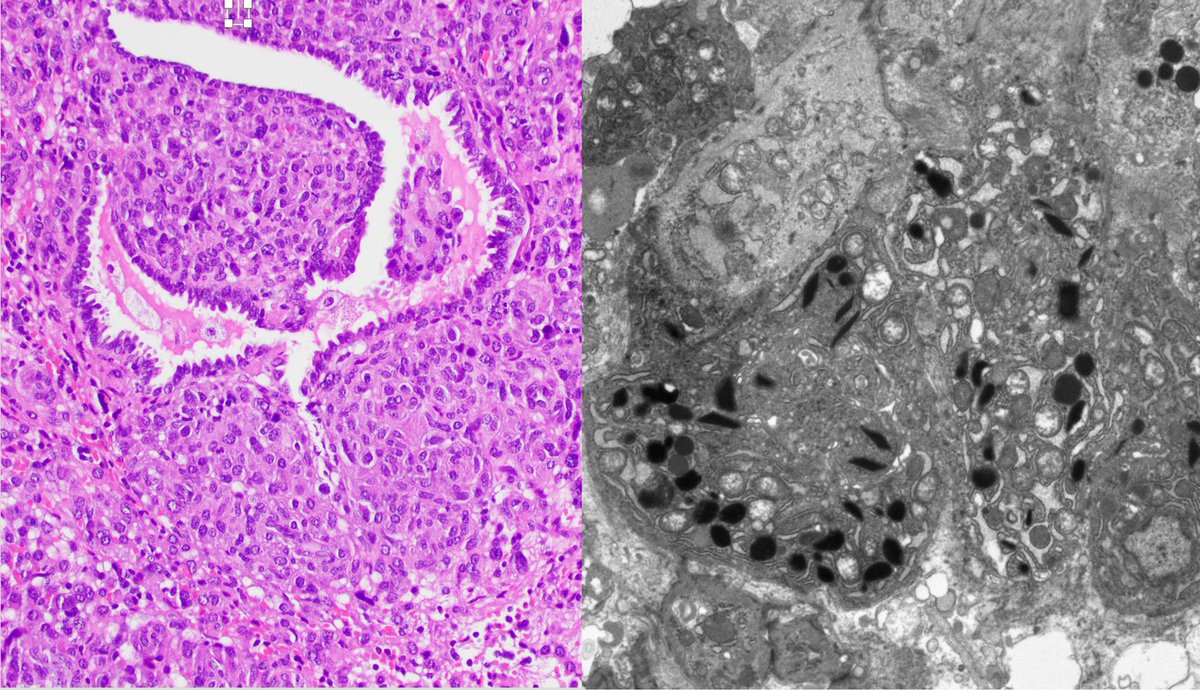

Case 5 Reninoma/Juxtaglomerular cell tumor. Neoplasm of renin-secreting cells. Renin+, vimentin+, CD34+, and CD117+. Electron microscopy shows rhomboid crystals of renin protogranules.

Case 5

Reninoma/Juxtaglomerular cell tumor. Neoplasm of renin-secreting cells. Renin+, vimentin+, CD34+, and CD117+. Electron microscopy shows rhomboid crystals of renin protogranules.